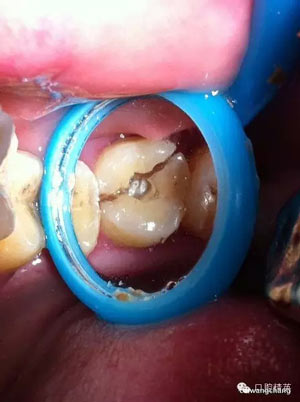

復(fù)位后可見基本對齊

玻璃離子墊底

超硬樹脂材料呈啞鈴狀充填,觀察1-2周無反應(yīng)給予牙體預(yù)備烤瓷冠修復(fù)